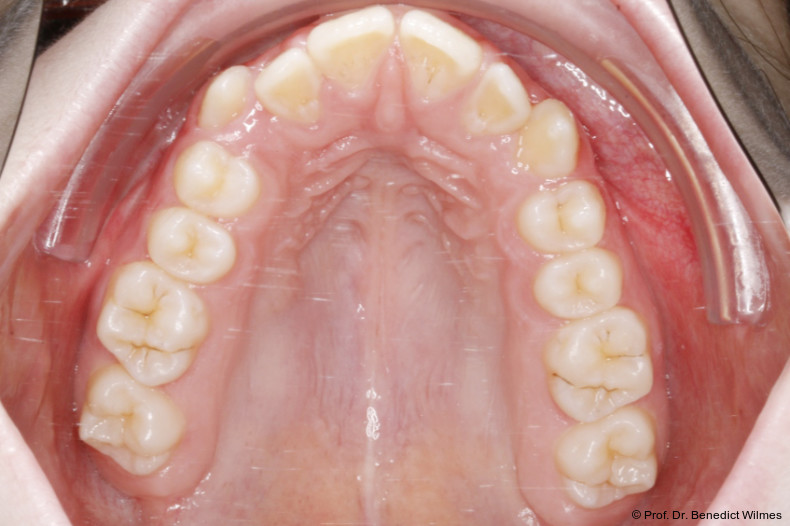

Die Shells wurden mit lichthärtendem Kom­posit befestigt. Nach Expansion des Oberkiefers (Abb. 5a–f) erfolgte eine Retentionsphase von neun Monaten, in der die Hybrid Hyrax in situ belassen wurde.

Nach dieser Rentionszeit wurde die Hybrid Hyrax entfernt und ein Scan zur Herstellung der Molarenintrusionsapparatur (digitale Mause­falle) durchgeführt. Die beiden Miniimplantatköpfe lassen sie dabei sehr gut scannen, so­genannte Scan-Bodies sind in der Regel nicht mehr notwendig. Die digitale Mousetrap-­Appa­ratur besteht aus zwei Teilen (Abb. 6):